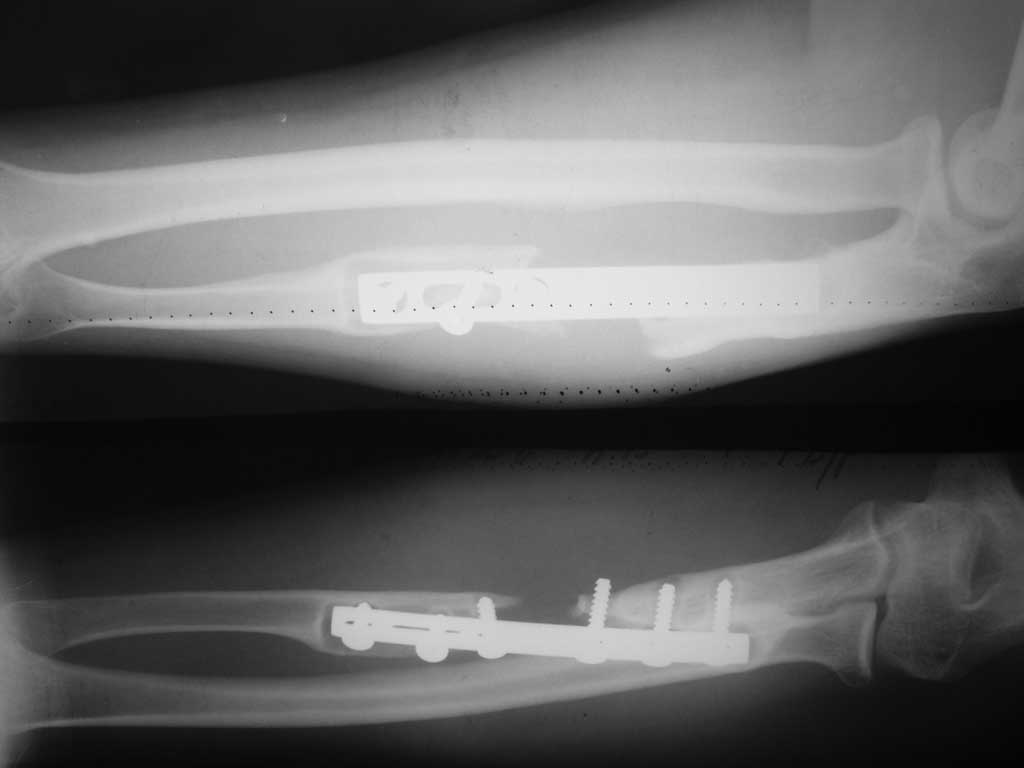

лизис локтевой кости после МОС.

Уважаемые коллеги прошу Вашего совета.Больной 33 лет прооперирован 2 года назад. Предыдущих снимков нет.

Планирую резекция кости в пределах до здоровой кости с замещением дефекта тутопластом с МОС пластиной с блокируемыми винтами.

При первичной фиксации допущены грубые технические ошибки. Скелетизация привела к лизису, а неадекватная фиксация привела к образованию ложного сустава предплечья с дефектом.